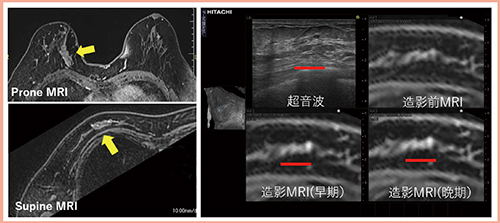

症例3は,乳房A領域にNMEを認めるが(図4左←),超音波像以上にMRIの造影域が内側に広がっているように思われた。RVSにて造影域の広がりが確認できたため(図4右■),RVSガイド下にマーキングを行い乳房温存術を施行した。主病巣はDCIS,断端は陰性であった。

図4 症例3(68歳):乳房A領域にNMEを認めた症例